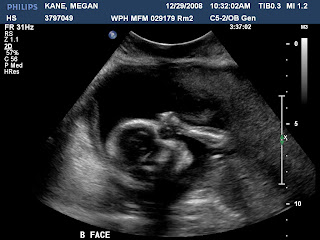

Our little boy's face!

Wax on, Wax Off...our little ones are regular karate kids! We went to meet with the specialist for the first time today and had an ultrasound (14 weeks and 2 days). It was amazing, but I think the coolest part of the experience was seeing how active our little ones are already. One of them literally did a flip...it was wild. The are definitely busy kicking and punching away, but I can't feel too much yet. We are pretty sure they will be fighting over space soon and if you have siblings you know this will continue for the rest of their/our lives. I can see the road trips now...Mom/Dad he's touching me! Oh the vacations we will have...